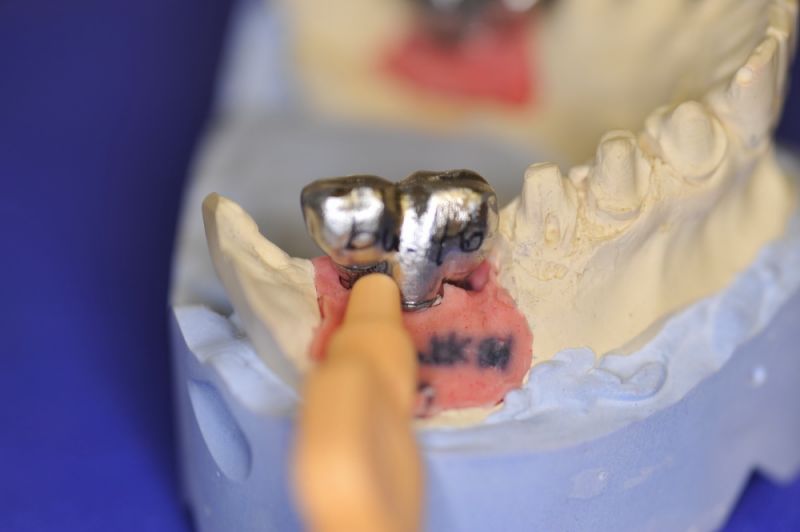

1. Notwendigkeit einer implantatgestützten Kronenversorgung mit der Vorgeschichte, dass die Patientin eine Vielzahl von Behandlern aufgesucht hatte, die eine Implantation im Unterkiefer als nicht durchführbar einschätzten.

2. Extrem schlechte knöcherne Verhältnisse im Unterkieferseitenzahnbereich, die sich intraoperativ noch einmal als ungünstiger darstellten, als bereits in den Voruntersuchungen erkennbar.

3. Sehr dünne Implantate, die von ursprünglich zwei je Kieferhälfte auf letztendlich drei je Kieferhälfte umgeplant werden mussten.